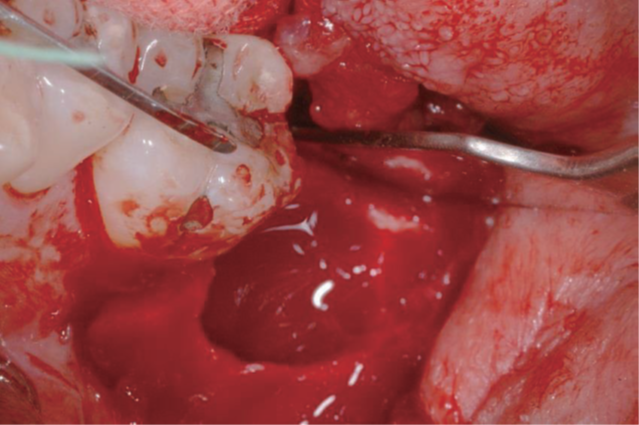

Bone resorption on the buccal and lingual side

Pre-Op view

GBR and suture with granulation tissue